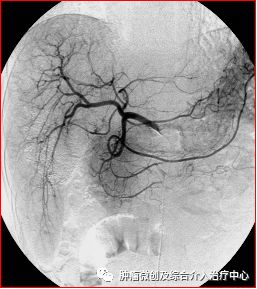

图2. 以导管超选择肿瘤的“犯罪血管”,缓慢注入化疗药与碘化油混合乳剂。

图5、6. 一肝癌患者,栓塞前造影显示肝右叶巨大团块样肿瘤染色(图中发黑处),通过3次肝动脉化疗栓塞,肿瘤不再显影,较前明显缩小。